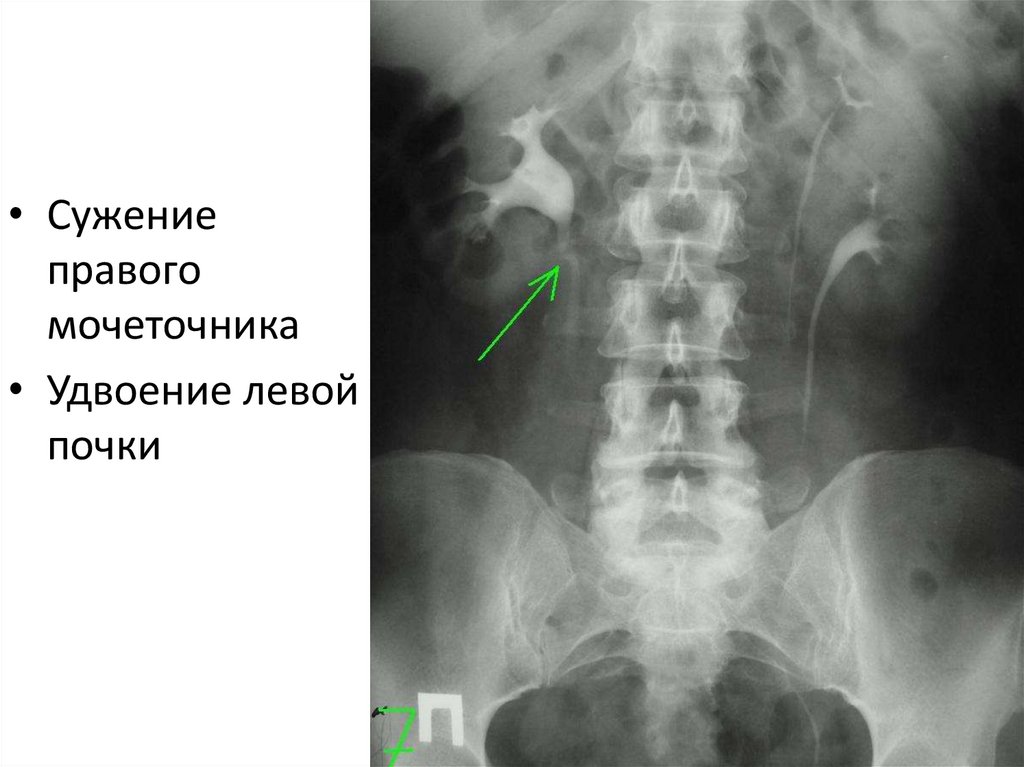

• Сужение

правого

мочеточника

• Удвоение левой

почки